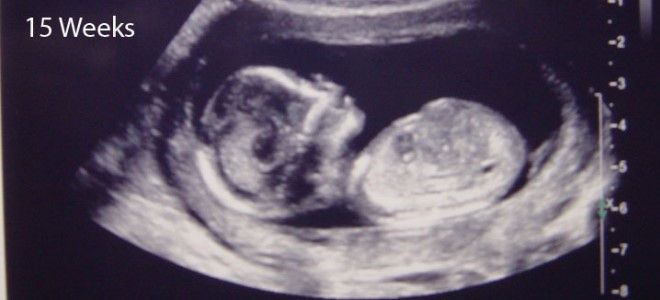

УЗИ 15 недель беременности

Первый скрининг необходимо провести до конца 13-й недели беременности, но не позже 15-й недели. В процессе этого обследования врачи также выполняют ультразвуковое исследование, которое может быть повторено на 15-й неделе.

Во время процедуры врач снова обращает внимание на пол ребенка: на 15-й неделе наружные половые органы становятся различимыми. Однако их визуализация не всегда возможна. Существенное значение имеет положение плода в момент исследования.